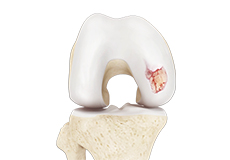

Articular Cartilage and Menisci of the Knee

Movement of the bones causes friction between the articulating surfaces. To reduce this friction, all articulating surfaces involved in the movement are covered with a white, shiny, slippery layer called articular cartilage. The articulating surface of the femoral condyles, tibial plateaus and the back of the patella are covered with this cartilage. The cartilage provides a smooth surface that facilitates easy movement.

Within the knee joint, between the femur and tibia, are two C-shaped cartilaginous structures called menisci. Menisci function to provide stability to the knee by spreading the weight of the upper body across the whole surface of the tibial plateau. The menisci help in load-bearing i.e. it prevents the weight from concentrating onto a small area, which could damage the articular cartilage. The menisci also act as a cushion between the femur and tibia by absorbing the shock produced by activities such as walking, running and jumping.